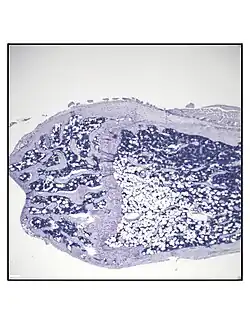

Secção histológica representativa da porção distal do fêmur de um camundongo C57BL/6 saudável de 16 semanas de idade, demonstrando uma quantidade típica de adipócitos na medula óssea.